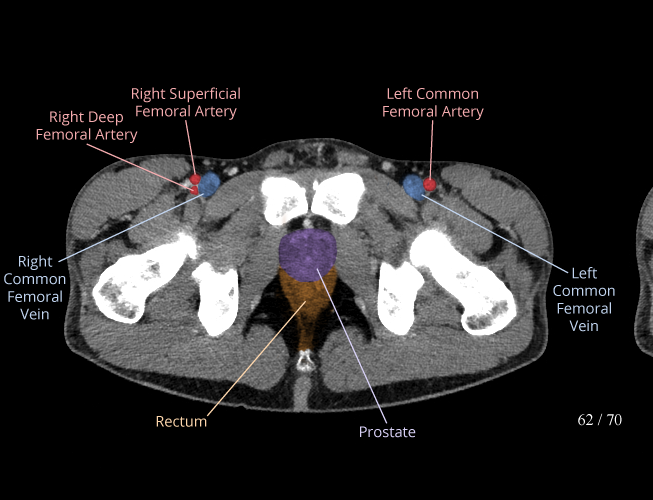

Pelvis

Covers pelvic MRI anatomy.